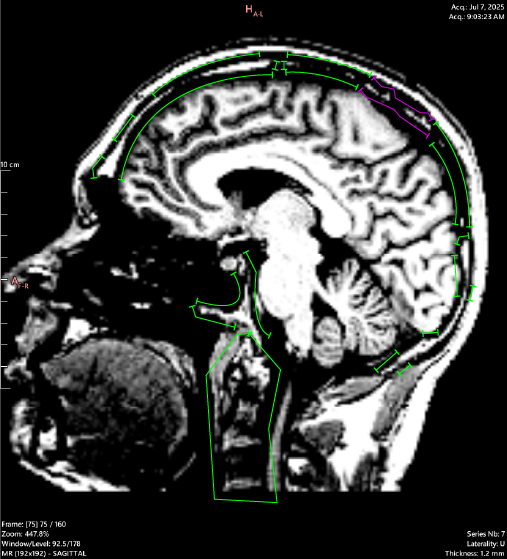

Corresponding MRI slices (JULY 2025):

JULY 2025:

T1 Sagittal